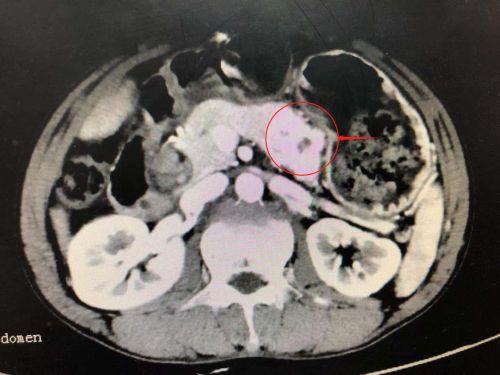

ct上可以清楚地看到胰腺肿瘤(红圈内)。

ct显示肝内外胆管均有结石。

CT检查发现,患者除肝内外胆管结石,胰腺体尾部还有一个5×3×2cm3大小的肿瘤。一边是亟待解决的全肝结石,另一边是不得不处理的胰腺肿瘤。汪新天主任医师及陈晨副主任医师多次组织开展科内讨论和术前评估,制订详尽的诊疗计划后,决定迎难而上,一次手术解决肝脏及胰腺两大疾患,使患者免受多次手术之苦。